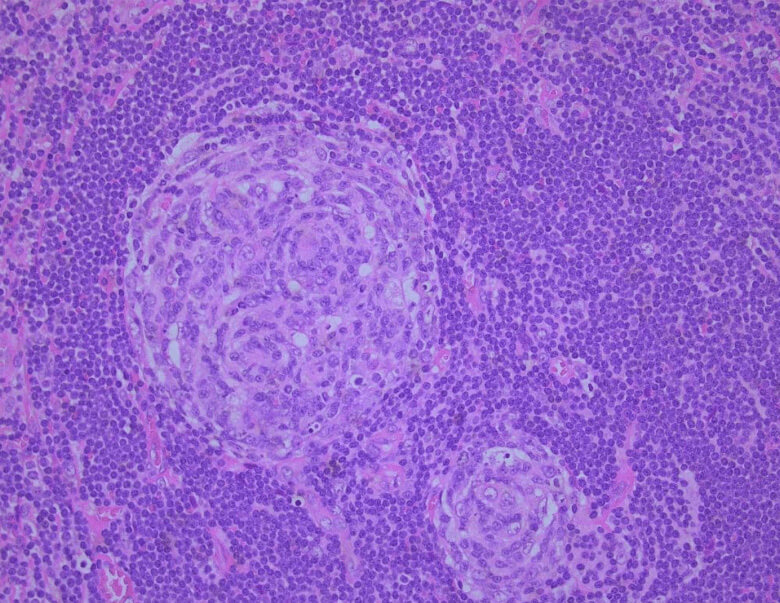

Castleman Disease

Castleman Disease (CD) is a term that describes three immune system disorders that display similar lymph node changes when assessed under a microscope.1

Received a lymph node biopsy that needs evaluating for CD / iMCD?